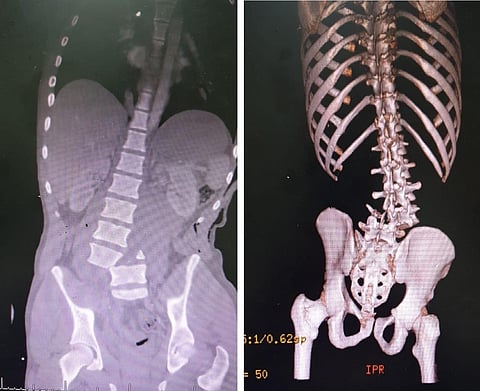

تعامل مستشفى الملك عبدالله ببيشة بنجاح مع حالة شاب إثر تعرضه لحادث مروري أدى إلى إصابته بكسر مع خلع بين الفقرتين الرابعة والخامسة وكان يعاني ضعفًا شديدًا في حركة الأقدام.

وتفصيلاً، قرر الفريق الطبي المعالج إجراء عملية جراحية عاجلة وبعد إجراء الفحوص الطبية اللازمة أدخل المريض غرفة العمليات الساعة الواحدة صباحًا، وتم عمل إجراء للخلع وتثبيت للفقرات، وبحمد الله تحسنت حالة المصاب من ناحية الحركة وعودته للمشي وهو بصحة جيدة وفي طور خروجه من المستشفى بمشيئة الله.